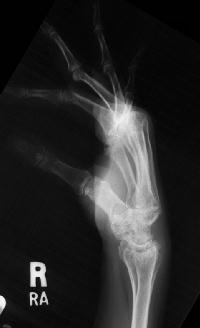

Clinical Example: Rheumatoid arthritis with DRUJ and radiocarpal involvement

Rheumatoid arthritis has many forms of presentation. This patient has bilateral severe radiocarpal and distal radioulnar joint involvement, with relative sparing of the metacarpophalangeal and interphalangeal joints.

The radiolunate joint did not spontaneously fuse on this side, allowing a greater degree of ulnar translation of the carpus. Note the severe cystic carpal changes.